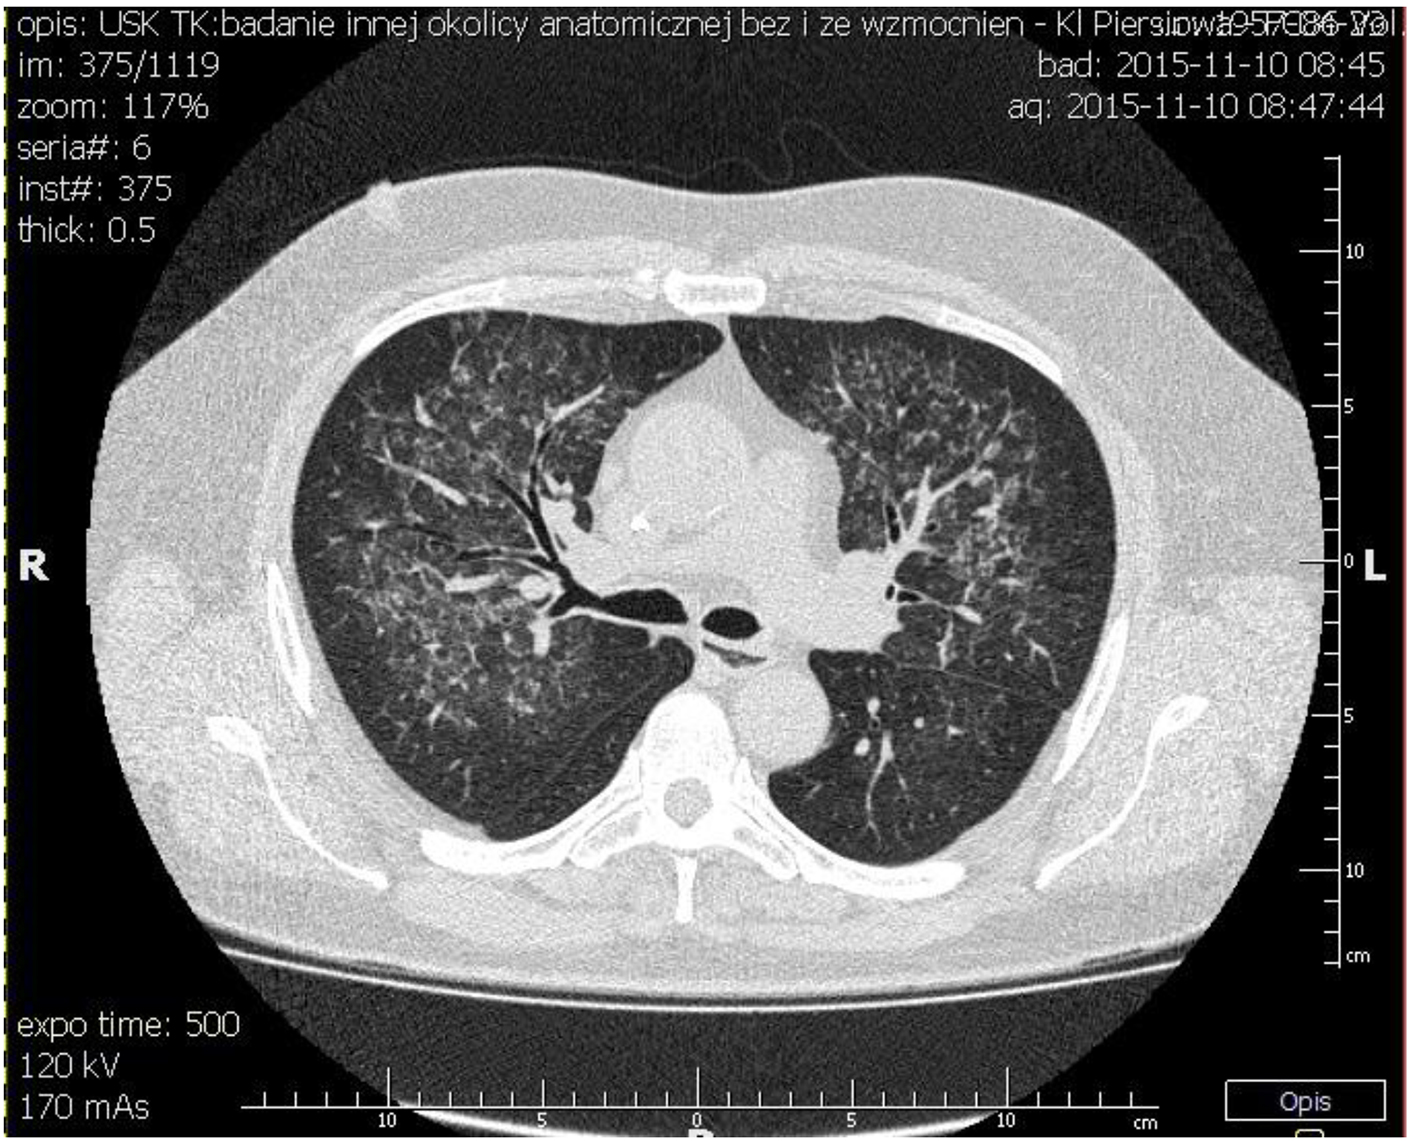

The patient was transferred to our institution for further workup of pulmonary-renal syndrome. Serologic tests for ANA, pANCA and anti-GBM antibodies were all negative except anti-proteinase 3 antibody (cANCA) at very low titers. Ultrasonography examination revealed kidney of normal size with no anatomic abnormalities, so the procedure of kidney biopsy was performed. Necrotizing crescentic rapidly progressive glomerulonephritis (RPGN) with linear pattern for immunoglobulin G along the entire GBM in immunofluorescent staining was identified. In three of six glomeruli, large cellular crescent and fibrinoid necrosis of capillaries were described (Figs. 2 and 3). The patient’s respiratory status started to deteriorate and the episodes of mild hemoptysis appeared. Chest computed tomography (CT) revealed bilateral, coalescent airspace opacities and extensive ground glass appearance (Fig. 4).

![]() Click for large image | Figure 4. Chest CT showing bilateral, coalescent airspace opacities and extensive ground glass appearance spreading from bronchi. |